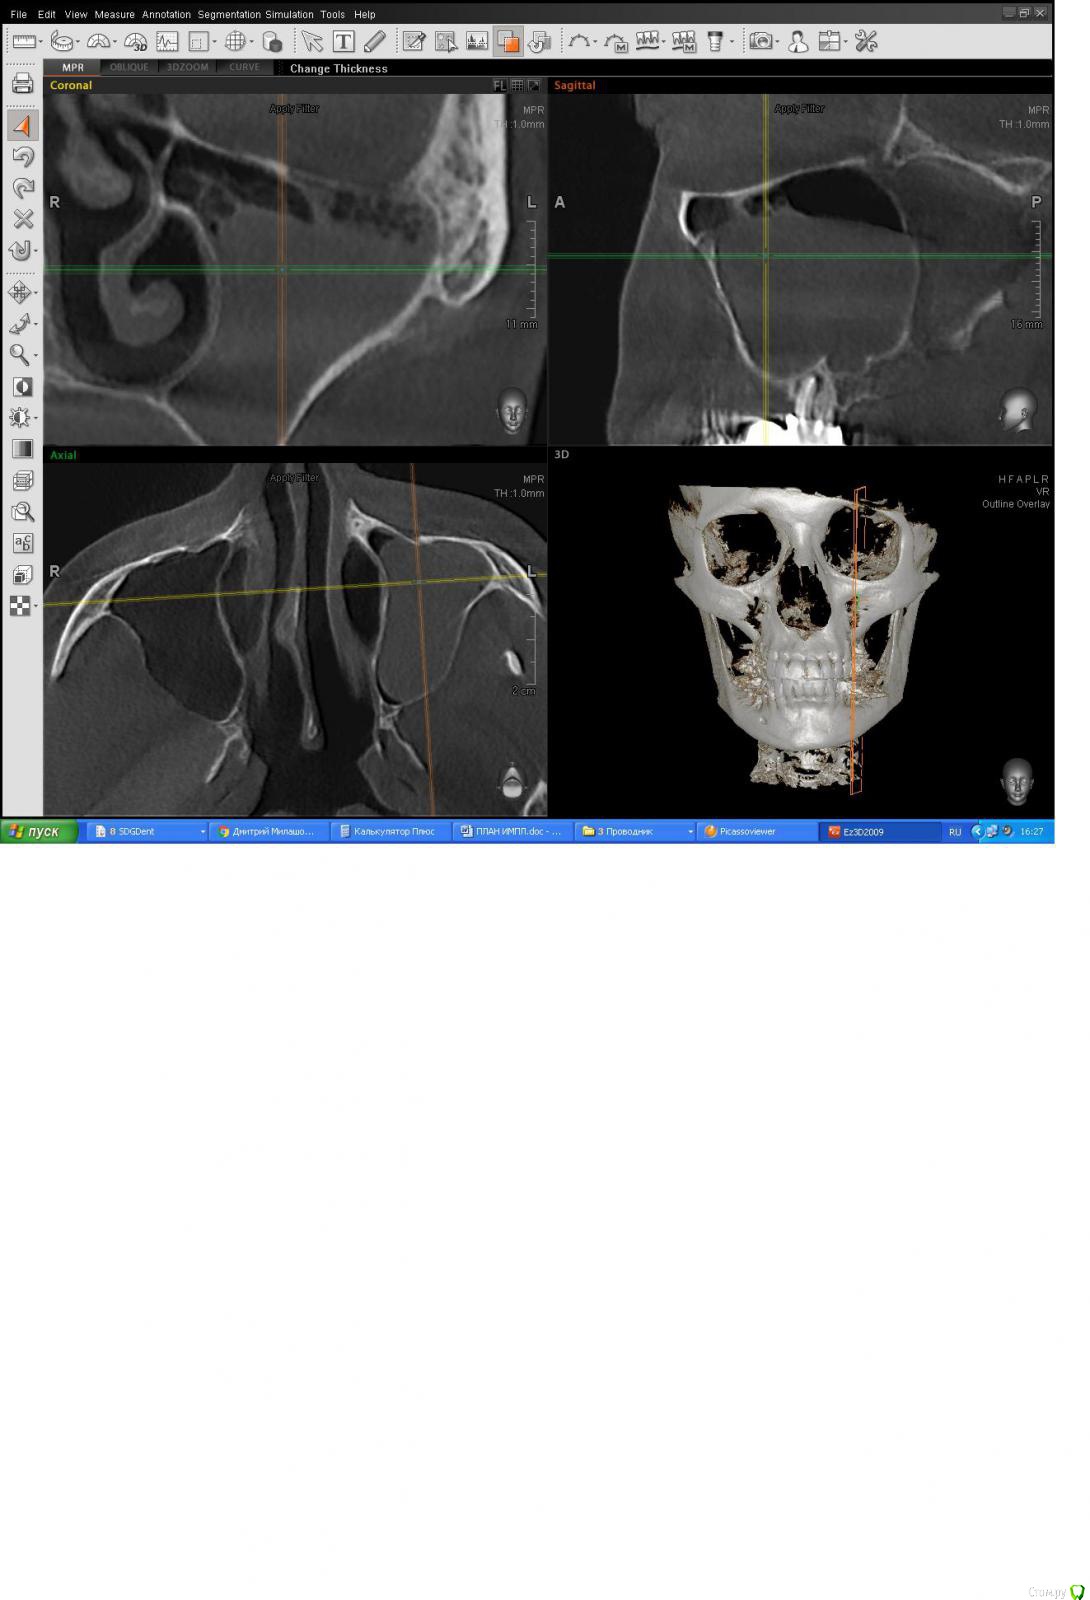

Bier Опубликовано 15 марта, 2017 Поделиться Опубликовано 15 марта, 2017 синус делать с таким образованием нельзя. Можете конечно сами его удалить. Делаете окно чуть выше, сначала опорожняете кисту шприцем, потом вытягиваете остатки отсосом. Затем делаете синус. Ссылка на комментарий

DoktorDre Опубликовано 16 марта, 2017 Автор Поделиться Опубликовано 16 марта, 2017 Спасибо, коллеги. То есть там есть жидкость, по- любому,и это не просто полип. Да, я видел удаление таких кист,( Чиапаско?) но наверное браться не буду, т.к сам не делал. кстати, она легко отделаться от шнайдеровой? Ссылка на комментарий

АнтонТЛТ Опубликовано 16 марта, 2017 Поделиться Опубликовано 16 марта, 2017 Уберите сначала зубы, через 2 месяца сделайте кт. Может образования в пазухе уже и не будет. 1 Ссылка на комментарий

DoktorDre Опубликовано 16 марта, 2017 Автор Поделиться Опубликовано 16 марта, 2017 Уберите сначала зубы, через 2 месяца сделайте кт. Может образования в пазухе уже и не будет.Может. Но оно уже там года три. И с зубами сейчас не сообщается Ссылка на комментарий

medunitsa Опубликовано 16 марта, 2017 Поделиться Опубликовано 16 марта, 2017 И всё-таки, уберите сначала зубы. 1 Ссылка на комментарий